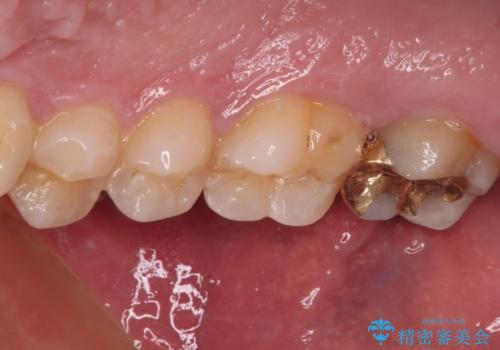

- 近医にて、銀歯の周りの歯が欠けてむし歯のようになっていると言われたとのことで来院された患者様です。

非常に咬合力が強く、銀歯やセラミックのような堅い素材では歯にダメージがかかり、治療を繰り返す可能性が高いと思われたので、ゴールドインレー(白金加金インレー、PGAインレー)にて、治療中の歯と銀歯が装着されている歯を修復治療することとしました。